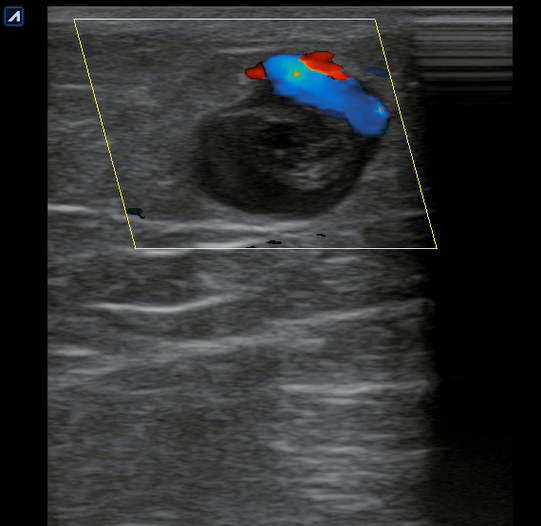

Se realiza ecografía clínica en consulta donde observamos a nivel inguinal adecuada compresibilidad de vena femoral y relleno con Doppler color. Cayado de safena libre y compresible. A 7 cm de distancia del cayado se aprecia, en territorio de safena, dilatación no compresible de la misma, contenido intraluminal ligeramente ecogénico y ausencia de Doppler color compatible con trombosis venosa superficial de 19 cm de distancia. Se estudia recorrido donde se observa en zona de dilataciones varicosas material ecogénico con ausencia de paso de Doppler alternando con zonas de paso parcial. En tercio distal de muslo comienza a desaparecer. Vena femoral profunda, poplítea y perforantes sin datos de trombosis.